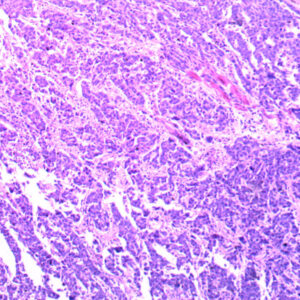

Advanced 100pcs human pathology teaching slides wholesale, university standard, Factory Outlets

Advanced 100pcs human pathology teaching slides wholesale, university standard, Factory Outlets

The Pathology teaching slides we offer are professionally hand-mounted, accurately stained, and individually labeled. Our microscope pathology slides are great for medical students, It has an excellent introduction to human disease in microscopy. The Pathology teaching slides are cover-slipped and preserved in cedarwood oil. All slides are carefully labeled for easy reference and are arranged in a fine plastic box with a separator. This pathology teaching slide set includes 14 systems of human diseases. It is excellent for educational use and is perfect for all levels of medical student study including home school programs.